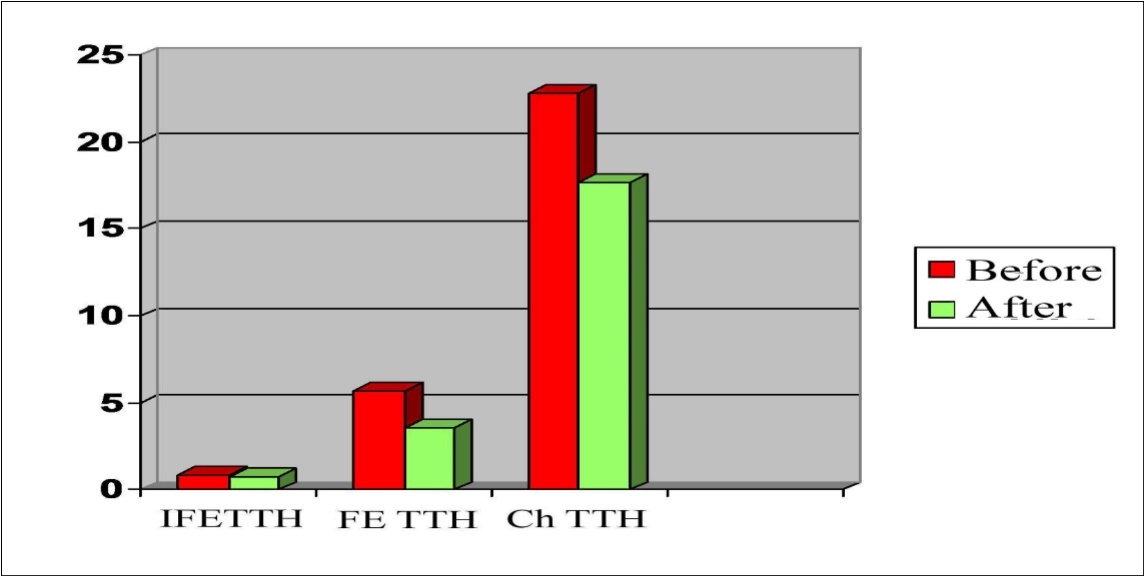

The asymmetry of the maximum systolic blood flow velocity (Vs) in the paired arteries within 20-30% was considered a violation of cerebral hemodynamics, which was detected in 38.7% of patients. An increase in Vs was noted in MCA in patients with Ch TTH and FE TTH compared with the control group (Figure 1, Figure 2A and B).

Figure 1.Parameters of Vs (cm/c) in the main cerebral arteries in a patients with TTH.

The pharmacotherapeutic effect of Noofen on the dynamics of blood flow indices in the main cerebral arteries is shown in Figure 8. The average value of the Vs in all groups before and after treatment was differented not significantly.

Figure 8.Dynamics of Vs in MCA, ACA, PCA in a patients with TTH during treatment with Noofen